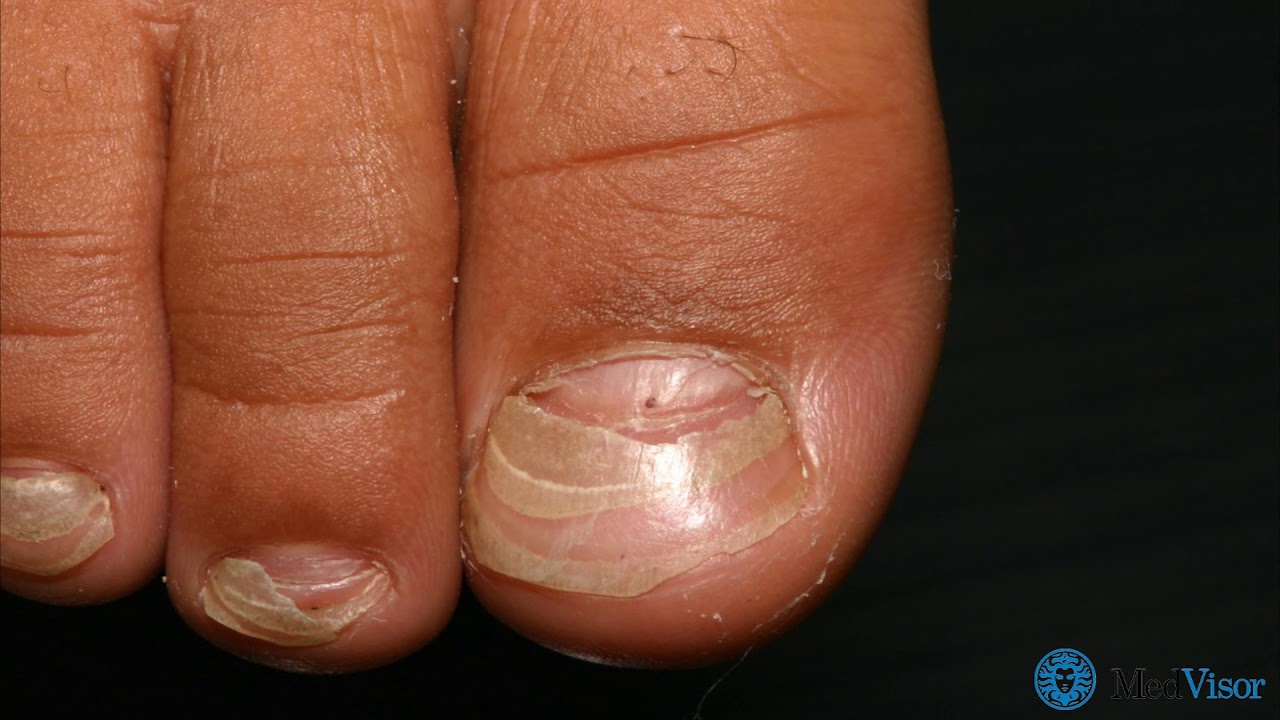

Как выглядит псориаз ногтей?

Псориаз на ногтях рук может проявляться различными симптомами, включая появление борозд на ногтевой пластине, изменение цвета ногтя, утолщение или деформацию ногтей. Борозды Бо-Рейля представляют собой вертикальные полосы или борозды на ногтях, которые могут быть одной из характерных особенностей псориаза на ногтях. Изменения цвета ногтя также могут быть заметны у пациентов с этим состоянием, включая желтоватый, беловатый или красноватый оттенок ногтей. Важно обращать внимание на такие изменения и консультироваться с дерматологом для диагностики и назначения соответствующего лечения.

Борозды Бо-Рейля – это один из характерных симптомов псориаза на ногтях рук. Они представляют собой вертикальные полосы или бороздки на ногтевой пластине, которые могут быть видны невооруженным глазом. Эти борозды могут быть разного размера и глубины, их наличие указывает на изменения в структуре ногтя, вызванные псориазом.

Борозды Бо-Рейля обычно формируются из-за нарушений в процессе роста ногтя, вызванных воспалением и гиперплазией клеток кожи. Их появление может сопровождаться утолщением ногтевой пластины и изменением ее формы. Пациенты могут заметить, что ногти становятся хрупкими, ломкими и менее эластичными из-за нарушений в структуре.

Изменения цвета ногтя

Изменения цвета ногтя могут быть одним из симптомов псориаза на ногтях рук. Обычно здоровые ногти имеют розоватый оттенок, но при поражении псориазом они могут измениться. Ногти могут стать желтоватыми, коричневыми или даже сероватыми. Иногда на ногтях появляются пятна или полосы другого цвета, что является признаком нарушения здоровья ногтей. Эти изменения могут быть сопровождаться изменением текстуры ногтей, их толщины и формы. Важно обратить внимание на такие изменения и консультироваться с дерматологом для диагностики и назначения соответствующего лечения.